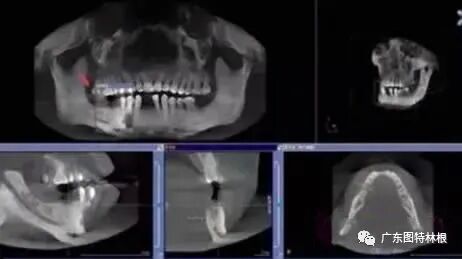

先要做一个口腔全景片、颌骨CT等。

查看口腔的具体情况,是否有炎症、牙槽骨吸收等情况。然后,医生会询问患者全身的病史,可能需要查血常规、出凝血时间、血压、血糖、乙肝5项、脉搏等。确定能手术后,才会诊断去模、指定种植牙方案。(第一次大约1个多小时)